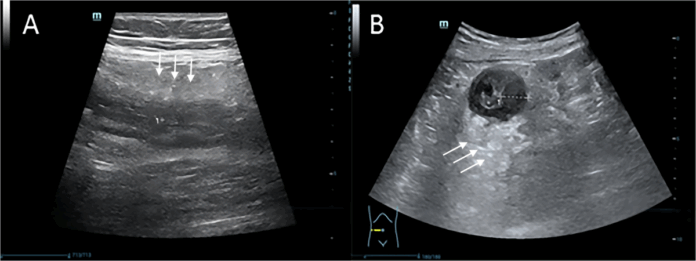

In contrast, VTIQ ultrasound is a non-invasive method that provides real-time information about tissue stiffness, which is needed to assess fibrosis and strictures. This allows clinicians to more effectively differentiate fibrosis from inflammation, which is a crucial factor for selecting the correct therapy and avoiding unnecessary surgical interventions.

The study analyzed data from 63 patients with the active phase of Crohn’s disease using the Mindray Resona R9T ultrasound system. Researchers focused on measuring Shear Wave Velocity (SWV) and Young’s Modulus—these two parameters are indicators of intestinal tissue stiffness. The obtained indices were compared with the endoscopic “gold standard” (SES-CD score), which is used to assess the severity of stenosis. The accuracy of all results was confirmed by expert radiologists.

Shear Wave Velocity was found to be the strongest prognostic marker for intestinal stenosis, with a high diagnostic accuracy (AUC 0.838).

By jointly using these ultrasound indicators, the diagnostic accuracy was further increased (AUC 0.878). This combination fully confirmed the reliability of endoscopy in detecting stenosis and significantly improved the non-invasive detection of the disease.